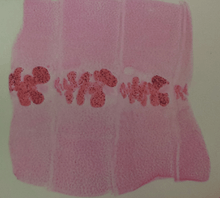

| Proglottids of D. latum | |

The adult worm is composed of three fairly distinct morphological segments: the scolex (head), the neck, and the lower body. Each side of the scolex has a slit-like groove, which is a bothrium for attachment to the intestine. The scolex attaches to the neck, or proliferative region. From the neck grow many proglottid segments which contain the reproductive organs of the worm. D. latum is the longest tapeworm in humans, averaging ten meters long. Adults can shed up to a million eggs a day.

In adults, proglottids are wider than they are long (hence the name broad tapeworm). As in all pseudophyllid cestodes, the genital pores open midventrally.

Diagnosis is usually made by identifying proglottid segments, or characteristic eggs in the feces.[7] These simple diagnostic techniques are able to identify the nature of the infection to the genus level, which is usually sufficient in a clinical setting.[4] However, when the species needs to be determined (in epidemiological studies, for example), restriction fragment length polymorphisms can be effectively used. PCR can be performed on samples of purified eggs, or native fecal samples following sonication of the eggs to release their contents.[4] Another interesting potential diagnostic tool and treatment is the contrast medium, Gastrografin, introduced into the duodenum, which allows both visualization of the parasite, and has also been shown to cause detachment and passing of the whole worm.[10]